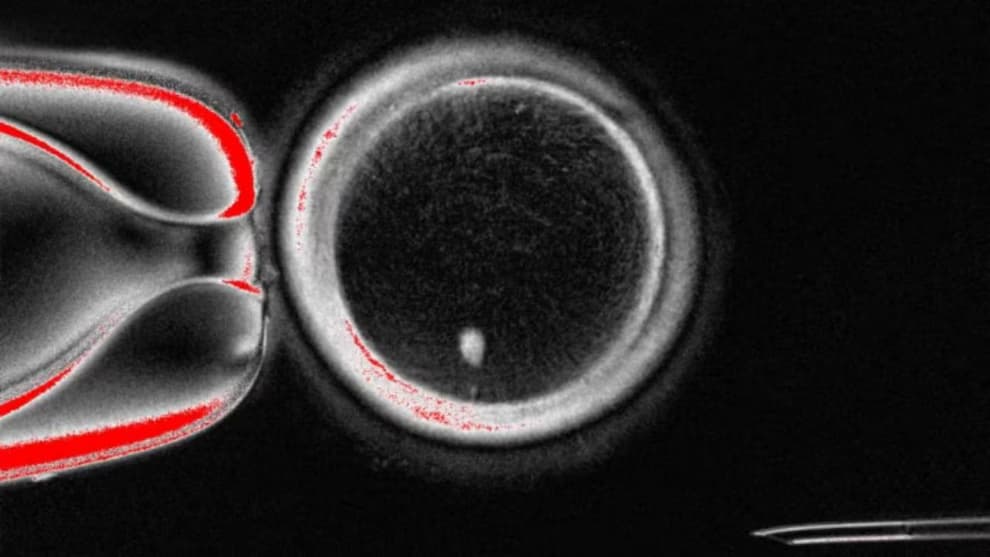

دانشمندان دانشگاه علوم پزشکی و سلامت اورِگان (OHSU) موفق شدند با بهره‌گیری از فناوری کلونینگ، از سلول‌های پوستی و تخمک‌های اهدایی، تخمک انسانی تولید کنند. این دستاورد می‌تواند امیدی تازه برای زنان نابارور و حتی زوج‌های همجنس‌گرا ایجاد کند تا صاحب فرزندانی با ارتباط ژنتیکی شوند. با این حال، متخصصان تاکید دارند که ورود این روش به مرحله درمانی دست‌کم ۱۰ سال زمان خواهد برد.

روش کار دانشمندان چگونه بود؟

در این پژوهش، هسته سلول‌های بالغ به تخمک‌های اهدایی که هسته‌شان حذف شده بود منتقل شد. DNA واردشده در یک فرآیند خاص، سلول‌ها را مجبور کرد نیمی از کروموزوم‌های خود را کنار بگذارند. این بازآرایی، مرحله‌ای حیاتی برای آمادگی تخمک جهت لقاح محسوب می‌شود.

پروفسور شوخرات میتالیپوف، سرپرست تیم تحقیق، این روش نوین تقسیم سلولی را «میتومیو‍ز» نامید و گفت: «طبیعت دو نوع تقسیم سلولی به ما داده بود، ما نوع سومی را ابداع کردیم.»

در این پژوهش ۸۲ تخمک تولید شد که با روش لقاح آزمایشگاهی (IVF) بارور شدند. اما تنها ۹ درصد از آنها توانستند به مرحله بلاستوسیست برسند، در حالی‌که در شرایط طبیعی این رقم حدود یک‌سوم است. هیچ‌یک از جنین‌ها پس از این مرحله پرورش داده نشدند.